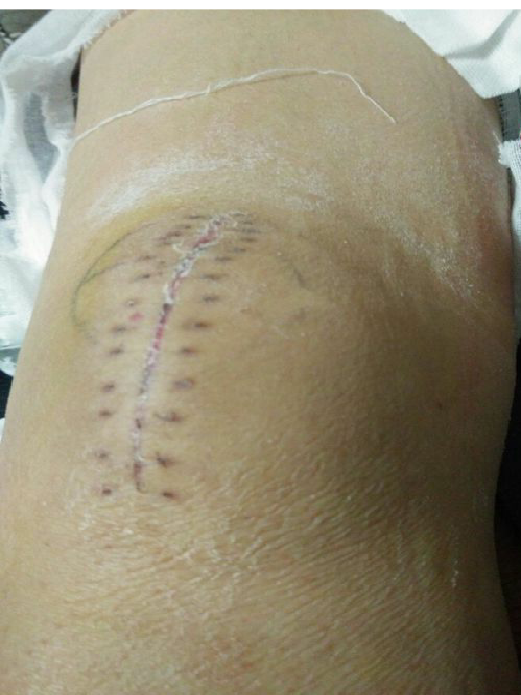

术后切口照片(无需缝合)

病房照(创口小,仅4个。最大的内下口约4MM)

术后复查

再次对比传统切口